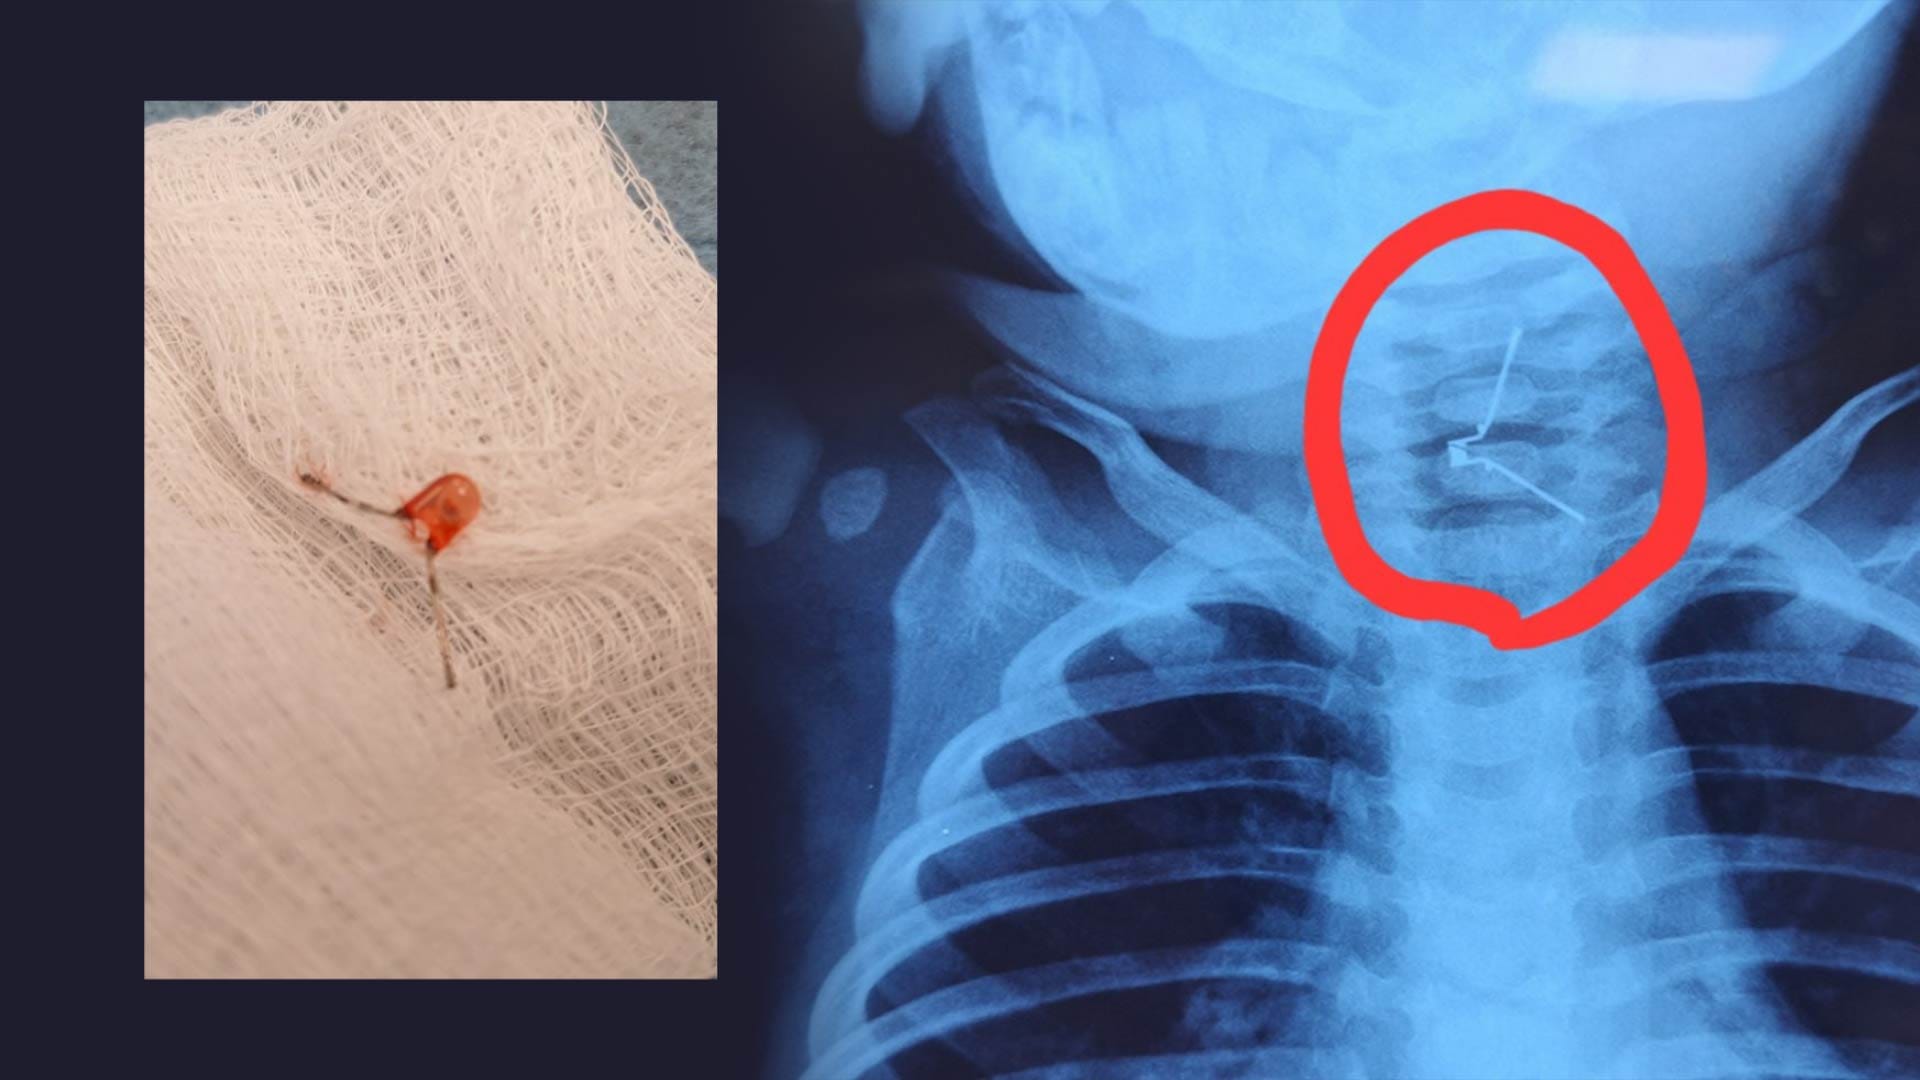

ئەو گڵۆپەی لە سوورێنچکی یوسفی تەمەن یەک ساڵ دەرهێنراوە

منداڵێک لە ئاکرێ دوای ئەوەی گڵۆپێکی بچووک قووت دەدات ڕاستەوخۆ ڕەوانەی نەخۆشخانە دەکرێت و نەشتەرگەرییەکی دەگمەنی بۆ دەکرێت، بەمەش ژیانی لە مردن ڕزگار دەکرێت.

چیرۆکی سەرەکی: شەوی 28ـی 3ـی 2024 منداڵێکی بچووک کە تەمەنی 9 مانگ دەبێت، لە کاتی یاریکردن گڵۆپێکی بچووک دەچێتە قوڕگییەوە، کاتژمێر 10ـی شەو ڕەوانەی نەخۆشخانەی فریاکەوتنی ئاکرێ دەکرێت، لەوێ پێی دەگوترێت دەبێت ڕاستەوخۆ نەشتەرگەری بۆ بکرێت چونکە گڵۆپەکە لە قوڕگیدا ماوەتەوە، دواتر پەیوەندی بە نەخۆشخانەی هیڤی دەکرێت و منداڵەکە بەرەو ئەوێ دەنێردرێت، ستافی نەخۆشخانەکە پێش گەیشتنی منداڵەکە، ژووری نەشتەرگەری ئامادە دەکەن و لەگەڵ گەیشتنی منداڵەکە بە نەخۆشخانە، نەشتەرگەری بۆ دەکەن و ژیانی ڕزگار دەکەن.

لێدوانی فەرمی: د.نزار بەکر، بەڕێوبەری نەخۆشخانەی هیڤی بە ئاڤا میدیای ڕاگەیاند: کاتژمێر نزیکی یەکی شەو بوو نەشتەرگەرییەکە سڕکردنی گشتیی ئەنجامدرا و لەڕێگەی نازوورەوە گڵۆپەکەمان لە قوڕگی منداڵەکە دەرهێنا.

زانیاریی زیاتر: "مەترسیدارترین سەرکێشی لە تەمەنی منداڵاندا لەنێوان 9 مانگی بۆ 3 ساڵیدایە، چونکە لەو قۆناغی تەمەنەدا منداڵ بگات بە هەر شتێک قووتی دەدات، بۆیە دایکان ئاگادار دەکەمەوە، لەو تەمەنە منداڵەکانیان بە تەنیا جێ نەهێڵن و ئاگاداریان بن". دکتۆر نزار وادەڵێت.

پێدراوە ڕاستییەکان: لەماوی دوو ساڵی ڕابردوودا زیاتر لە 60 حاڵەتی لەم جۆرە لە نەخۆشخانەی هیڤی تۆمار کراوە کە پێویستییان بە نازوور هەبووە.